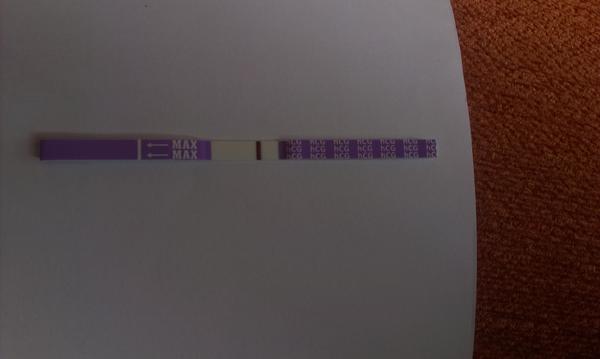

Slabý duch na teste

Ahojte zienky.. prosim vas o radu.. neviem ci to vidim len ja, alebo su tam naozaj dve ciarky??? 😒 ja tam vidim slabulilinkeho ducha na kazdom teste.. dnes som 27dc, mavam pravidelne 25dnovy cyklus, takze uz treti den mi meska mrcha.. uz dva tyzdne mi byva obcas trosku nevolno (ale zas neviem ci si to len namyslam alebo je to tak) prosim poradte mi, to cakanie ma ubija.. o dietatko sa snazime druhy mesiac, jedno dvojrocne uz mame 🙂

- Slabé ružové čiarky na domácich tehotenských testoch často predstavujú "ducha" alebo presvitajúce sfarbenie a nie vždy znamenajú ochytenie; odporúča sa opakovať test po vynechaní menštruácie alebo potvrdiť krvnými testami u lekára.

A: Diskusia uvádzala, že ide môže ísť o "ducha" alebo čiarku, ktorá po vyschnutí zmizne (tzv. evaporation line); odporúčaný postup je urobiť opakovaný test o pár dní alebo dať odobrať krv na hCG u lekára.

- Prečo sa niekedy na testoch objaví slabá ružová čiarka a nasledujúca menštruácia — ide o evaporation line, chemické tehotenstvo alebo technický problém s konkrétnou značkou?